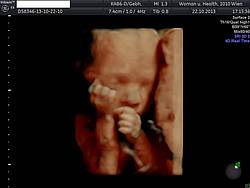

25. bis 28. SSW

Erneute Blutabnahme mit Bestimmung von Blutbild, Eisenspiegel, Hepatitis und bei fehlender Immunität Toxoplasmose und Zytomegalie.

Cervixultraschall zur Bestimmung der Gebärmutterhalslänge, Wachstumskontrolle des Kindes. Messung der Nabelschnurdurchblutung zur Überprüfung der kindlichen Versorgung.

Um die zweistündige Wartezeit optimal zu nutzen, führen wir die 3. Mutterkindpassuntersuchung sowie die interne Untersuchung im Rahmen des Zuckerbelastungstests durch.